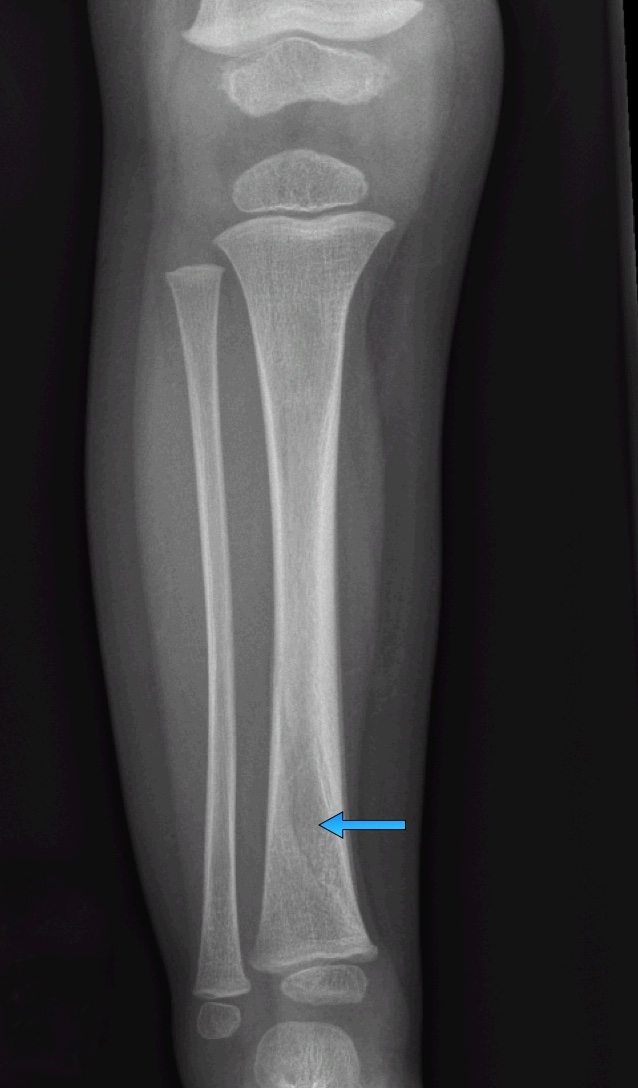

Answer: Toddler's Fracture

- Spiral or oblique non-displaced fracture of the distal tibia

- Very common in ambulatory toddlers, occurs with low energy falls or twisting injuries

- Initial radiographs are normal in 13-43% of cases, often a clinical diagnosis

- Present with focal tenderness, refusal to bear weight, pain on dorsiflexion, often minimal or no swelling

- Treatment is immobilization (long leg cast), no weigh bearing, orthopedics follow-up in 7-10 days